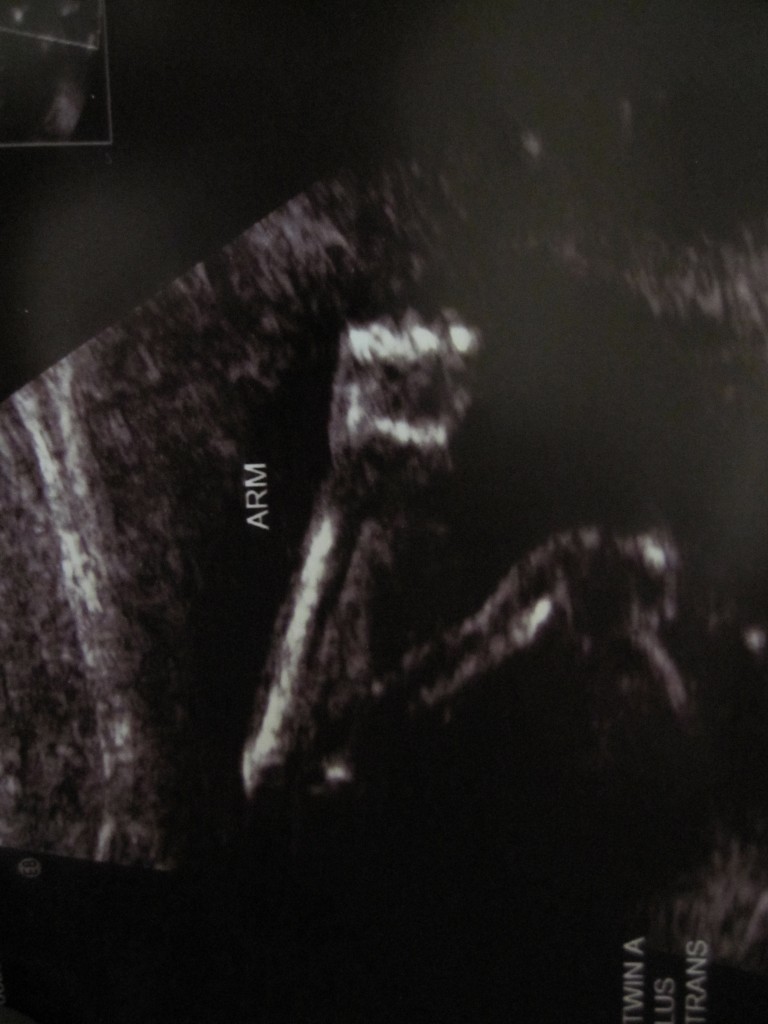

If you look closely, you can see she is smiling. (Baby B, 18wks)

Baby A at 18wks. Looking closely here you can see the umbilical chord. So cool.